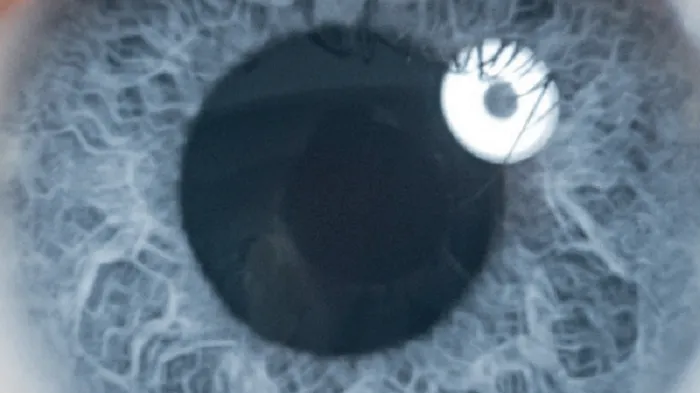

Elle est généralement envisagée en complément d’autres traitements de la surface de l’œil. La greffe de membrane amniotique est utilisée à la suite de graves brûlures, d’ulcères ou d’œdème de :

- la cornée : membrane transparente recouvrant l’avant de l’œil.

- la conjonctive : membrane transparente recouvrant la cornée et l’intérieur des paupières.

Appliquée sur les lésions de la surface de l’œil (cornée ou conjonctive), la membrane amniotique fonctionne comme un pansement. Elle libère ainsi les substances qui la composent et aide à :